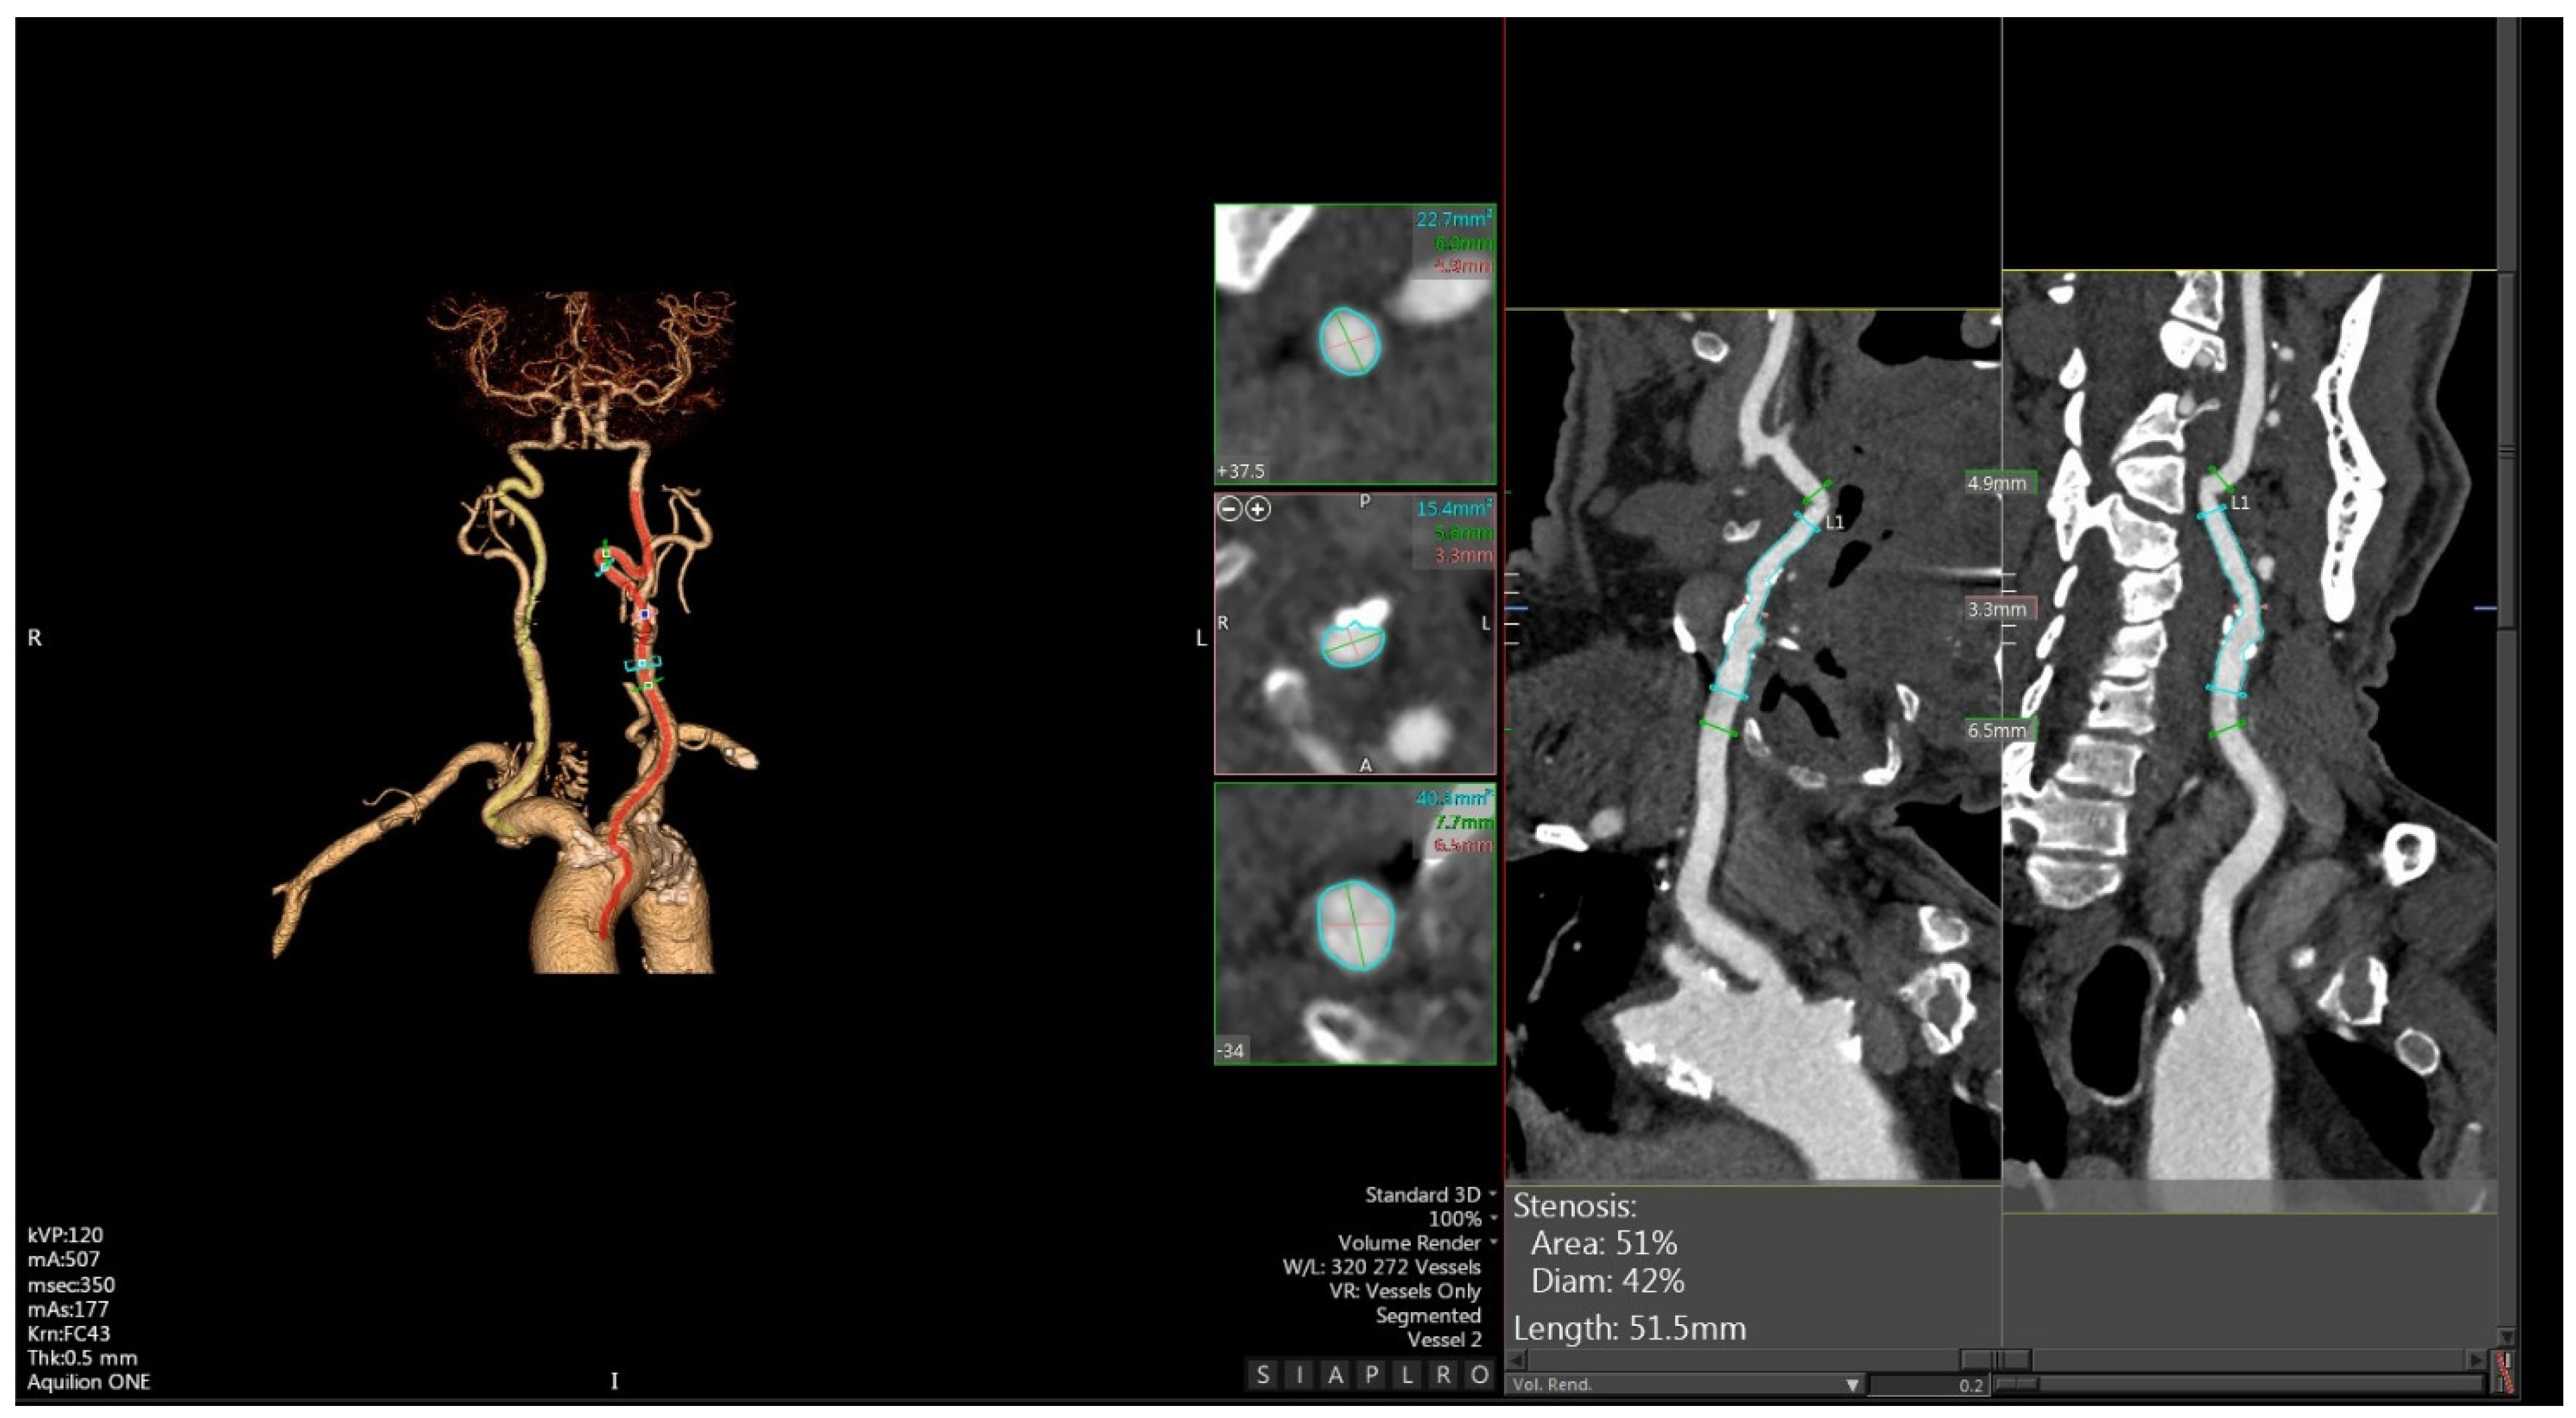

3. CTA